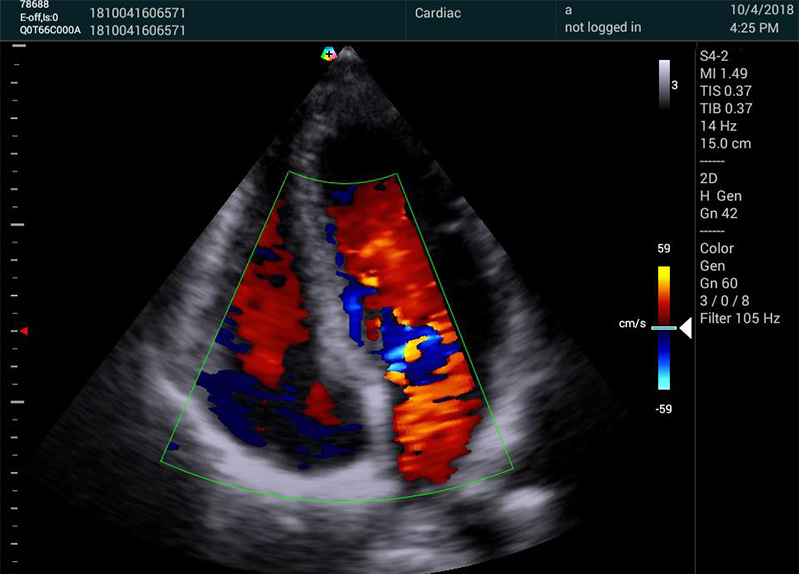

无论心血管、妇产、腹部、小器官应用,还是介入等专科应用,M20都能切换自如。

心脏应用方面,M20解剖M型模块M型取样线可360度任意旋转,可同时选取3条M型取样线,在方便快捷的进行心功能评估时,可以从不同阶段不同瓣口评估心肌运动。